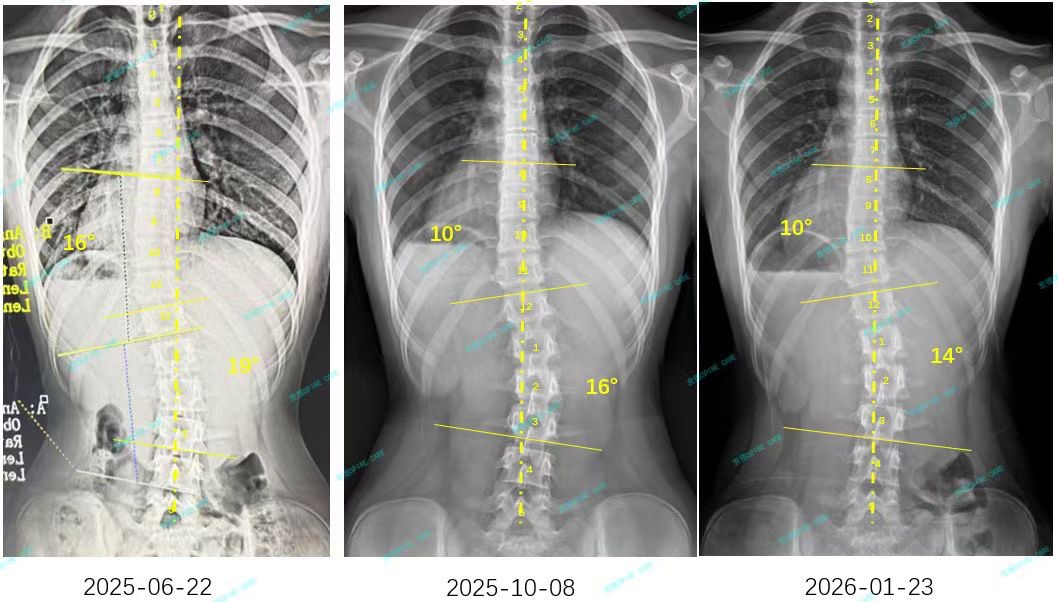

来自家长对衷德的评价(小逸妈妈)